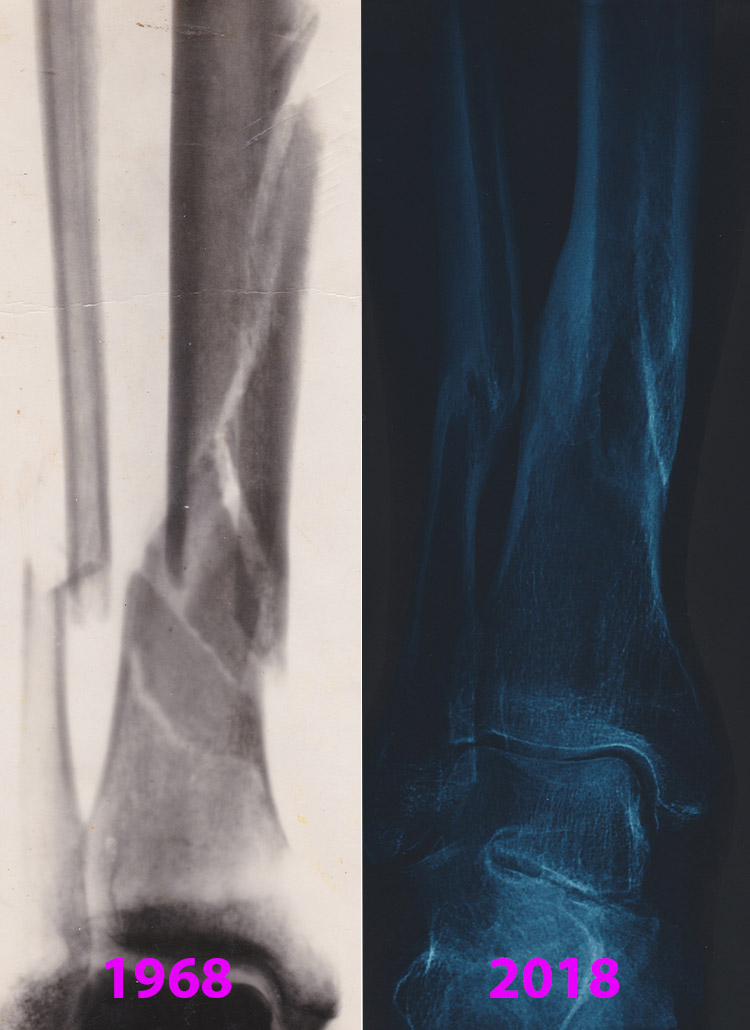

Holy crap, Dave, we weren’t ready for that! “Big break” in American lingo usually is a good thing... apparently not so much over there on the wrong side of the world :)

David ..shocking...not that you broke your leg ,,but the fact that you kept a set of X rays ? This has me thinking you must have been in some collisions while cycling too? I know I have twice. Once was a T-bone with a car on a side street and once was a knock down by a car side mirror.